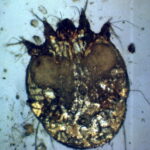

Histologic examination of a specimen containing a burrow reveals that the burrow in almost its entire length is located within the horny layer . Only the extreme, blind end of the burrow, where the female mite is situated, extends into the stratum malpighii . The mite has a rounded body and measures about 350 to 450 IJm in length and 250 to 350 IJm in width . |

Pathogenesis. Earlier scanning electron microscope studies revealed the keratinocytes around the burrow to be compacted, indicating that the mite physically forces its way in between the keratinocytes rather than chewing a passage (48). More recent studies, however, also using transmission electron microscopy, have found that the secretion of cytolytic substances by the mite as a contributing factor in advancing the parasite body through the skin in addition to mere compression (53). The cellular damage was greatest around the body, especially the mite capitulum. |